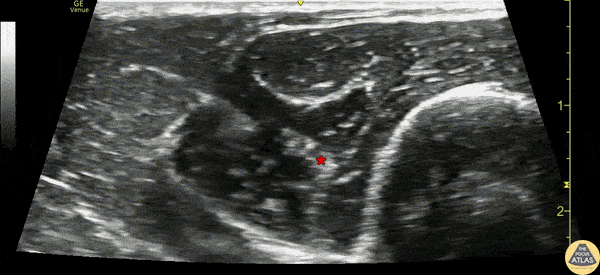

20s F presented with large complex laceration to the distal forearm after an assault. Ultrasound radial and median nerve blocks were performed at the elbow to facilitate washout and closure. This clip illustrates the radial nerve block, where the needle is entering from the posterolateral aspect of the upper arm, and anesthetic can be seen surrounding the radial nerve (*). Dr. Gabe Siegel Denver Health Residency in Emergency Medicine